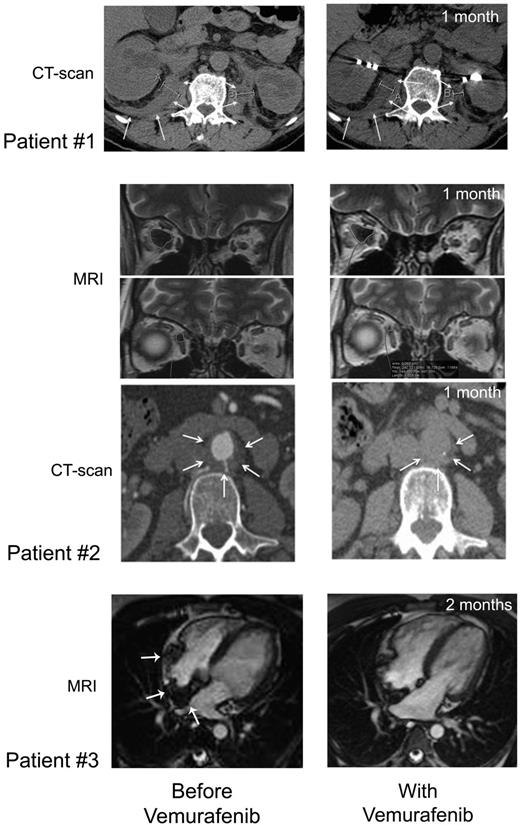

CT scan and MRI imaging assessment. Patient no. 1: Comparison of abdominal axial CT scans performed before (January 28, 2012; left) and on day 37 (May 23, 2012; right) of treatment showing regression of the infiltration around both kidneys (white arrows), evidenced by the decreased thickness (right kidney: 24.8 to 18.2 mm, left kidney 22 to 12.4 mm). Patient no. 2: Comparison of MRI performed before (left) and on day 36 (right) of vemurafenib treatment showing regression of ECD orbital infiltration. Comparison of abdominal axial CT scans performed before (March 29, 2012; left) and on day 39 (May 25, 2012; right) of vemurafenib treatment showing regression of the infiltration around abdominal aorta (white arrows): latero-aortic infiltration from 10.8 to 6.5 mm thick, and posterior infiltration from 6.5 to 4.6 mm thick. Patient no. 3: comparison of cardiac MRI, 4-chamber view: (A) February 21, 2012; see the infiltration of the atrial septum, the posterior wall and the free wall of the right atrium (white arrows); (B) July 19, 2012; note the regression of the infiltration.

Vemurafenib was started at 1920 mg/d (b.i.d.) on April 19, 2012 and was tapered to 960 mg/d from day 30 due to erythema, and was thereafter maintained at this dose. Within a few days of the initiation of treatment, itching disappeared. Evaluation on day 30 showed an improvement of creatinine (190 to 161μM), GGT (936 to 300 U/l) and alkaline phosphatase (644 to 177 U/l) values. On day 62, GGT was 183 U/l, PAL 146 U/l, and creatinine 170μM. CRP was normalized by day 30 (Figure 4), and remained under 5 mg/L on day 62. PET was performed after 30 days of vemurafenib treatment and the findings compared with those obtained 4 months earlier: there was a substantial improvement of all lesions (Figure 1), with a mean Standardized Uptake Value (SUV) change of −70% (range, −66% to −80%); the change within soft tissue and bone was similarly −70% (range, −51% to −78%; supplemental data, available on the Blood Web site; see the Supplemental Materials link at the top of the online article). Thoraco-abdominal CT after 37 days of treatment showed a significant reduction of periaortic infiltration (Figure 3). This cannot be attributed to PEG-IFN treatment, withdrawn on March 31, 2012, because several other markers clearly indicated that the patient was a nonresponder (high CRP values, hydronephrosis and pyelocalicial dilation, worsening of PET findings). Hydronephrosis and pyelocaliceal dilation resolved completely. Note that the PET assessment at 4 months showed that the decrease of FDG uptake had been sustained: uptake was lower than that observed after the first month (Figure 1). Aortic MRI after 4 months disclosed a marked regression of peri-aortic sheathing relative to that observed by CT-scan in May 2012. The CRP value remained low on day 123 of treatment (Figure 4).

After a few days, histiocytic skin lesions resolved (Figure 2), and the pain in the right eye disappeared such that morphine could be stopped. A new skin biopsy confirmed the absence of histiocytic infiltration of the epidermis and hypodermis. CRP was normalized by day 30 (Figure 4), and was 5.2 mg/L (N < 5) on day 48. PET 31 days after initiation of vemurafenib was compared with that performed 2 months earlier: the change in the mean SUV was −57% (range, −51% to −67%) and that in soft tissue and bone was −70% (range, −56% to −78%; Figure 1 and supplemental data). Orbit MRI on day 36 showed a 26% to 66% decrease of the retro-orbital infiltration (Figure 3 and supplemental data). Thoraco-abdominal CT on day 39 demonstrated a 30% to 40% decrease of the posterior and lateral peri-aortic infiltration (Figure 3), and the absence of the previously observed interlobular septa thickening, characteristic of pulmonary involvement of ECD. The CRP value remained below 5 mg/L on day 141 of treatment (Figure 4), and the patient was asymptomatic, with the absence of orbital pain.

Vemurafenib was administered at 1920 mg/d (b.i.d) from May 9 to May 29: the dose was tapered to 960 mg/d (b.i.d) due to pilar keratosis and erythema. One month later, the CRP level was 10 mg/L, the thickeness of xanthelasmas had diminished, and PET displayed significantly decreased uptake in the basilar region and by the long bones. In July 2012, the CRP value was normal. The most striking feature was the significant improvement of the cardiac MRI on July 19: right atrial wall infiltration had regressed substantially (Figure 3). On day 119 of treatment, the CRP value was still low, at 8 mg/L (Figure 4).